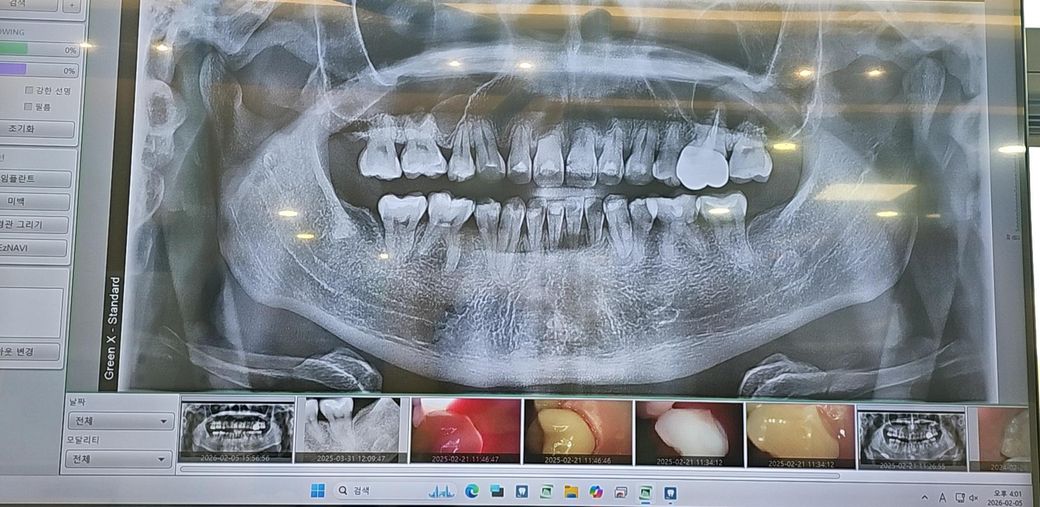

뜨거운 음식에 잇몸통증, 사진찍으면 이상없다고 합니다.

3주전부터 왼쪽 어금니 쪽 위아래 잇몸 안쪽이 뜨거운 음식을 먹을 때마다 너무 아파서 얼마 전 치과에 가서 사진도 찍고 검사를 받았는데 의사 선생님께서 보시더니 아무런 이상이 없고 치아 상태도 괜찮다고 스케일링만 받고 나왔습니다.

그런데 치과 다녀온 뒤로 시간이 좀 지나고 드문드문 아프다가 오늘 다시 뜨거운음식 먹을 때 통증이 심해서 전문가분들께 정확한 조언을 듣고 싶습니다.

사진도 올려봅니다.

교정을 해서 잇몸이 많이 약한 상태입니다.

일단 잇몸통증인지 치아통증인지 원인부터 감별이 되어야 하고요 뜨거운것에 통증은 보통 치아와 관련하여 비가역적치수염의 가능성이 있습니다